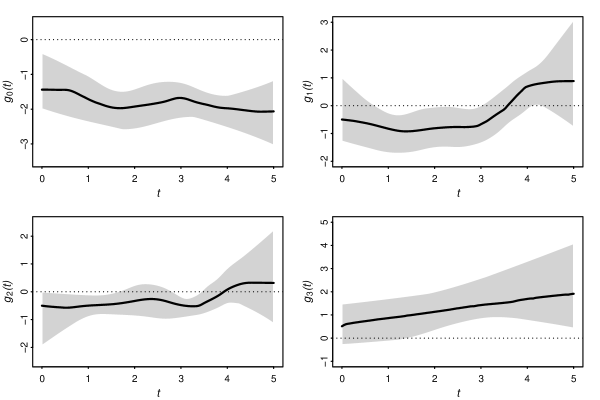

Figure 3 top left panel presents . Because its posterior mean (black line) is approximately horizontal and the 95% Credible Band (CB) lies, approximately, in , we can consider that HIV/AIDS individuals taking medicines correctly have a lower baseline hazard and do not suffer major changes over time. This plot seems to tell us that nowadays people living with HIV, if correctly treated, will have a large life expectancy. Indeed, May et al. (2014) have already noted this in a big study involving 21,388 patients in the UK. Some groups of HIV-positive individuals may expect to live a similar life span to that of the general population, others have reduced life expectancy due to the impact of late diagnosis and late initiation of the therapy. Unfortunately our dataset does not have information about the elapsed time since the infection until the treatment beginning. We only know that older people take longer to start the therapy. The top right panel shows that initially the individual random intercept, , does not have a significant effect on the hazard but after a short period of time, less than a year, individuals with CD4 counts at the study entry above the mean are at lower risk until, approximately, the begin of the third year when that initial value becomes negligible again. Indeed after a certain period of time it is expected that the initial values become less important. The bottom left panel shows that an individual with a positive time trend for the biomarker has a decreased hazard of death up to 3.5 years after diagnostic, approximately, because the 95% CB lies below the horizontal dotted line, . After that period the impact is lowered. Bottom right panel suggests that the higher the within-individual variability the higher the hazard of death and that effect is growing over the time, albeit only after 1.5 years approximately, because the horizontal dotted line, , is in the 95% CB before that period. Biologically this is understandable, because if after 1 or 2 years the CD4 counts variability doesn’t stabilize, that means that patient’s immune system is responding poorly to the treatment.

Have the possibility to incorporate time-dependent coefficients into a model is often a bonus. Without it we could not have given the interpretations to the coefficients that we gave above. Actually, the posterior estimates for and in model are, respectively, and , which leads us to gave the following explanation: during the patients follow-up, individuals with higher CD4 values at the study entry and with an upward trend for the CD4 trajectory have a decrease in their risk of death. But, due to the fact that our chosen model has time-dependent ’s we know now that after a certain period of time both the initial value and the trajectory trend become non-significant.